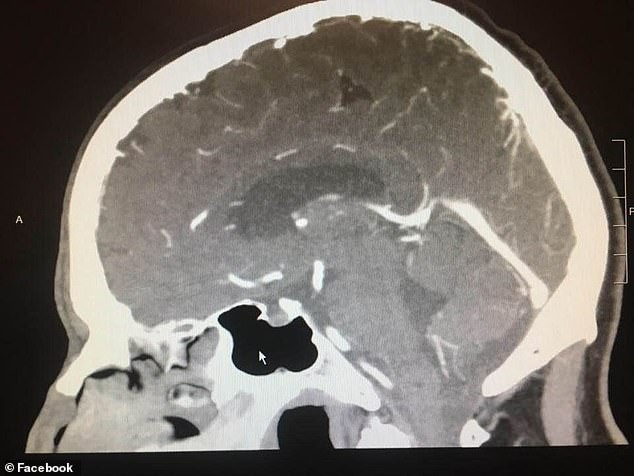

A Lodi városában élő Paul Wood rossz állapotban volt; állandó fejfájás gyötörte. Egy San Franciscói agysebész szerint Woodnak agyvérzése lehetett, a koponya CT-k tanulsága szerint pedig tumor volt az agyában.

A felvételen látható a daganat - jobb alsó sarokban egy fehér, kerek folt.